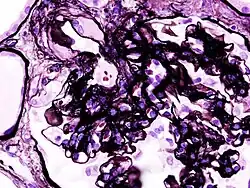

| Microscopic image of diabetic glomerulosclerosis, the main cause of nephrotic syndrome in adults. | |

_PAM.jpg)

Secondary causes of nephrotic syndrome have the same histologic patterns as the primary causes, though they may exhibit some differences suggesting a secondary cause, such as inclusion bodies.[24] They are usually described by the underlying cause, such as:

- Diabetic nephropathy: is a complication that occurs in some diabetics. Excess blood sugar accumulates in the kidneys, causing them to become inflamed and unable to carry out their normal function. This leads to the leakage of proteins into the urine.